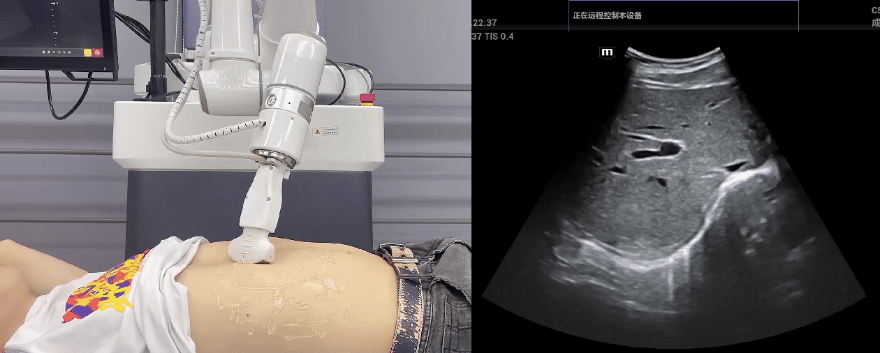

艾利特協作機器人搭載庫柏特自主研發的機器人遙操作、多模態數據采集與處理、機器人模仿學習、機器人力位控制等技術升級變革傳統超聲,可實現遠程+自主超聲掃查與診斷,從傳統遠程超聲僅能對話會診變革升級為能對話、能操作,使得基層患者可就近享受異地三甲專家掃診服務。實現專家端與患者端遠程連接,并支持專家端與多路患者端自由切換控制。

艾利特機器人末端搭載超生L13-3N線陣探頭,可以對淺表小器官和外周血管進行超聲檢查;搭建C5-1s凸陣探頭,可以對腹部(肝、膽、胰、腎等器官進行超聲檢查)

EC66協作機器人末端可搭載主流品牌高品質超聲儀,讓操作指令和影像低延遲、高精準、高保真傳輸,確保檢查可靠、醫患放心;智能力控等三重防護系統,確保患者舒適、安全。

艾利特協作機器人與超聲深度打通,最大程度保留醫生左右手同時操作傳統超聲的習慣,并改善其舒適性,超聲檢查實際應用場景展示如下:

肝臟、膽囊、胰腺掃查